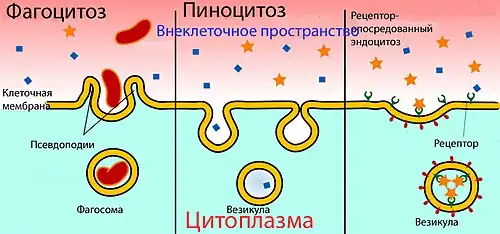

Другим отличием эндотелия церебральных капилляров от периферических является низкое содержание в них пиноцито́зных пузырьков (вези́кул)[9][32].

Везикулярный транспорт

Рецептор-опосредованный трансцитоз

С помощью рецептор-опосредованного трансцито́за происходит перенос больших молекул. На обращённой в просвет сосуда поверхности клетки расположены специальные рецепторы для опознавания и связывания определённых веществ[23]. После контакта рецептора с веществом-мишенью происходит их связывание, участок мембраны инвагинируется в полость клетки и образуется внутриклеточный пузырёк — везикула. Затем она перемещается к обращённой к нервной ткани поверхности эндотелиальной клетки, сливается с ней и высвобождает связанные вещества. Таким образом во внеклеточное пространство мозга переносятся состоящий из 679 аминокислот белок трансферрин массой 75,2 кДа[162], липопротеины низкой плотности из которых образуется холестерин[130][163], инсулин[164] и другие пептидные гормоны[23].

Абсорбцио-опосредованный трансцитоз

Одним из подвидов везикулярного транспорта является абсорбцио-опосредованный трансцитоз. Отмечается «прилипание» ряда положительно заряженных веществ (катионов) к отрицательно заряженной клеточной мембране с последующем образованием везикулярного пузырька и его переносом к противоположной поверхности клетки. Данный вид транспорта также называется катионным. Он проходит относительно быстрее рецептор-опосредованного трансцитоза[165][166][167][168].